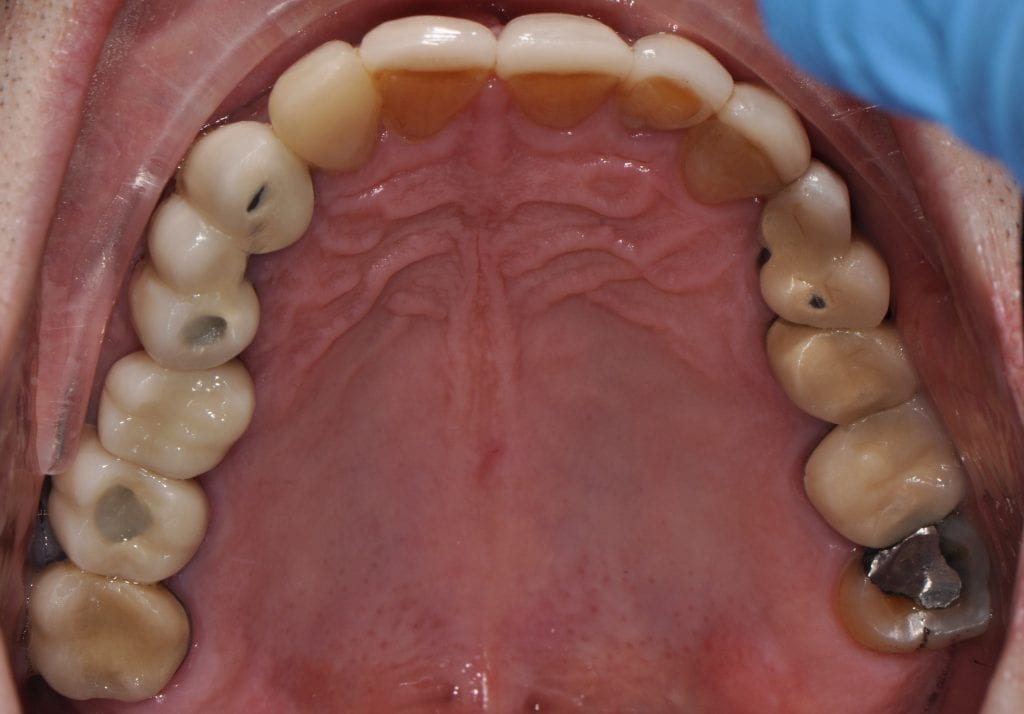

Pre-existing restorations that warranted replacement with an increase in vertical dimension.

Pre-existing restorations that warranted replacement with an increase in vertical dimension. The upper and lower arch were captured with the medit I500 and articulated together with enough clearance to accommodate new restorations and to restore the patient to an ideal tooth position.